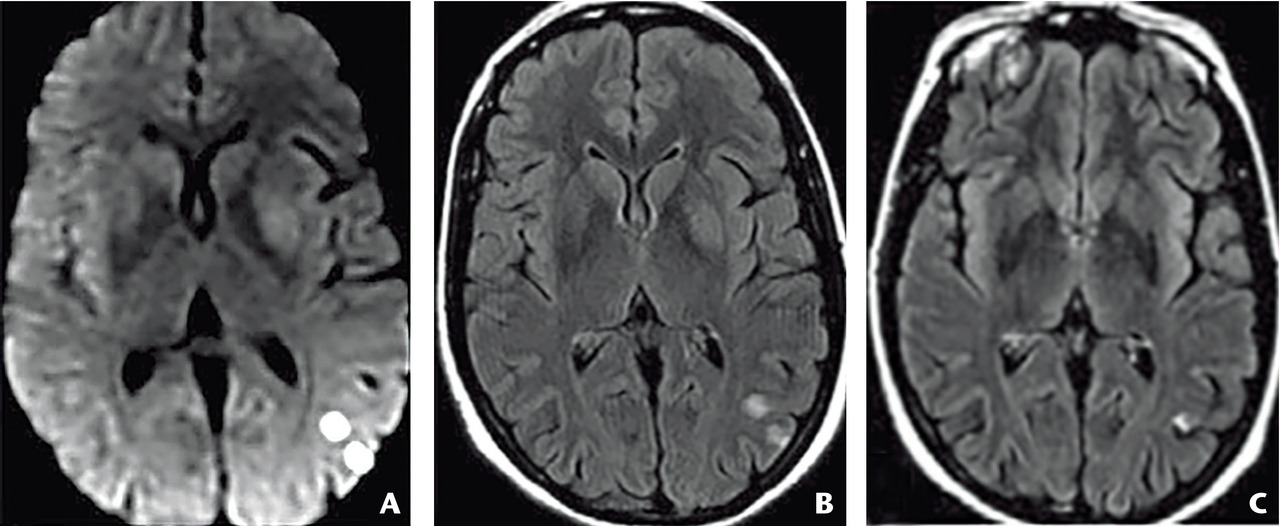

En effet, dans 5 % des cas, le déficit neurologique transitoire est dû à une hémorragie intracérébrale (fig. 1a, malformation vasculaire : cavernome) ou à d’autres maladies à risque hémorragique (fig. 1b, angiopathie amyloïde cérébrale).

Les principaux sont l’hypoglycémie, la crise épileptique partielle et l’aura migraineuse (tableau 1). L’examen clinique peut contribuer à les éliminer. L’IRM encéphalique (encadré 1) est un examen précieux pour poser le diagnotic (fig. 1).

L’IRM encéphalique est préférable à la tomo- densitométrie (TDM) parce que, contrairement à celle-ci, elle montre les lésions hémorragiques anciennes de petite taille.

La séquence de diffusion est indispensable ainsi que celle dite T2*-écho de gradient (encadré 1).

1. Intérêt de l’IRM encéphalique dans la pathologie neurovasculaire

Séquence de diffusion (DWI, Diffusion Weighted Imaging) : l’hypersignal traduit le ralentissement de la mobilité des molécules d’eau secondaire aux lésions ischémiques avec présence d’un œdème cytotoxique dès les premières minutes. La cartographie du coefficient apparent de diffusion (ADC, Apparent Diffusion Coefficient) permet une évaluation quantitative du mouvement, diminué (restriction), en cas d’ischémie.

Séquence T2*-écho de gradient : l’hyposignal traduit la présence d’hémosidérine, produit de dégradation de l’hémoglobine. Cette séquence permet la mise en évidence d’une hémorragie intracrânienne.

Autres séquences : FLAIR (évaluation morphologique du parenchyme cérébral) et ToF (imagerie vasculaire, notamment du polygone de Willis, sans injection de produit de contraste).